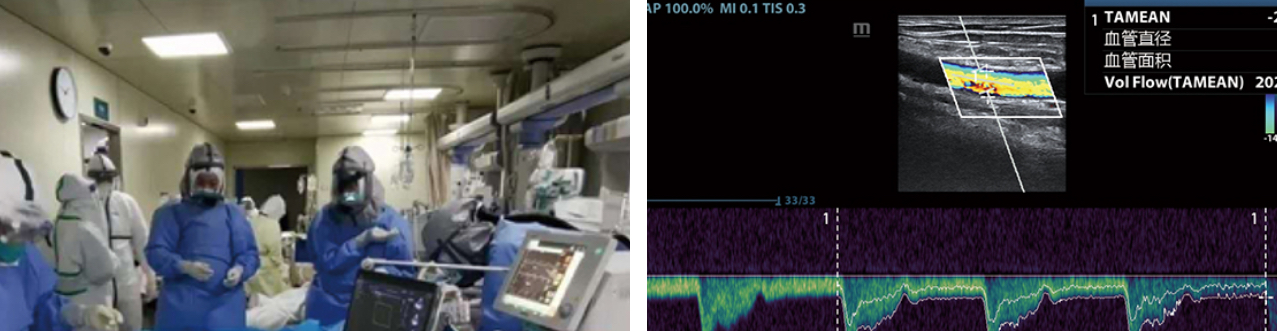

- 3. For ECMO, support vascular puncture, observe arteriovenous vessels and improve the efficiency of surgery